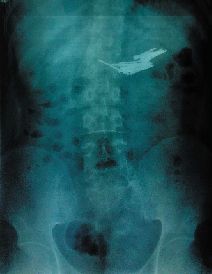

前晚10点38分拍摄的X光片,清晰地显示了19根钉子存在于少年体内。

拍出的X光片,成了这个急症室故事的清晰注脚。它显示:少年的胃下部靠近肠道的位置,有多根长约4.5厘米左右的铁钉状异物。仔细数了数,足有19根。

昨天下午,记者在医院看到了前晚拍摄的两张X光片。在X光片上,沈飞腹部位置的钉子清晰可见,19根钉子主要集中为两捆,并在不断位移。

急诊外科的杨医生告诉记者:“他主要是阵发性腹痛,但还能忍受。从现在拍出来的片子看,钉子应该还没有刺破肠壁。肚子按下去没有反跳痛,也未出现腹膜炎的症状。只是这根钉子一直在往下走,现在已经到了他的盆腔里。”杨医生估计,沈飞吞钉时可能做过一些处理,比如用胶带把尖利的地方包起来。

随着胃肠道的蠕动,昨天下午4点多的检查显示,钉子已经到了他的回肠部位。